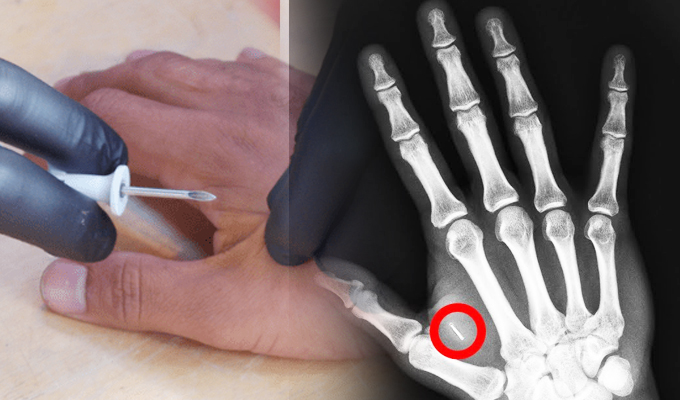

Cerca de 5.000 personas utilizan ya un implante NFC en su mano en sustitución de tarjetas físicas.

En Suecia unas 5.000 personas llevan en su mano implantado un dispositivo que utilizan en su día a día para viajar en tren, entrar en sus oficinas de trabajo o en el gimnasio, sacar fotocopias e incluso comprar aperitivos en máquinas expendedoras.

En la actualidad estos implantes se usa principalmente en tres ámbitos: para viajar en diferentes medios de transporte, en accesos a recintos y como medio de almacenamiento de información privada.